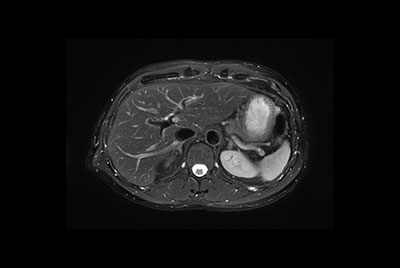

Liver MR imaging